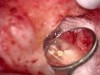

Accurate diagnosis is sometimes the most difficult aspect of daily clinical practice. CBCT has improved the trained practitioner's ability to find hidden periapical pathology, particularly in areas where structures such as the maxillary sinus and zygomatic arch, as well as thick cortical bone, can conceal periradicular lesions (Figure 7 and Figure 8).5-7

Fig 7. 2D radiograph of tooth No. 3.

Figure 7

Fig 8. 3D CBCT image of tooth No. 3 revealing hidden periapical pathology.

Figure 8